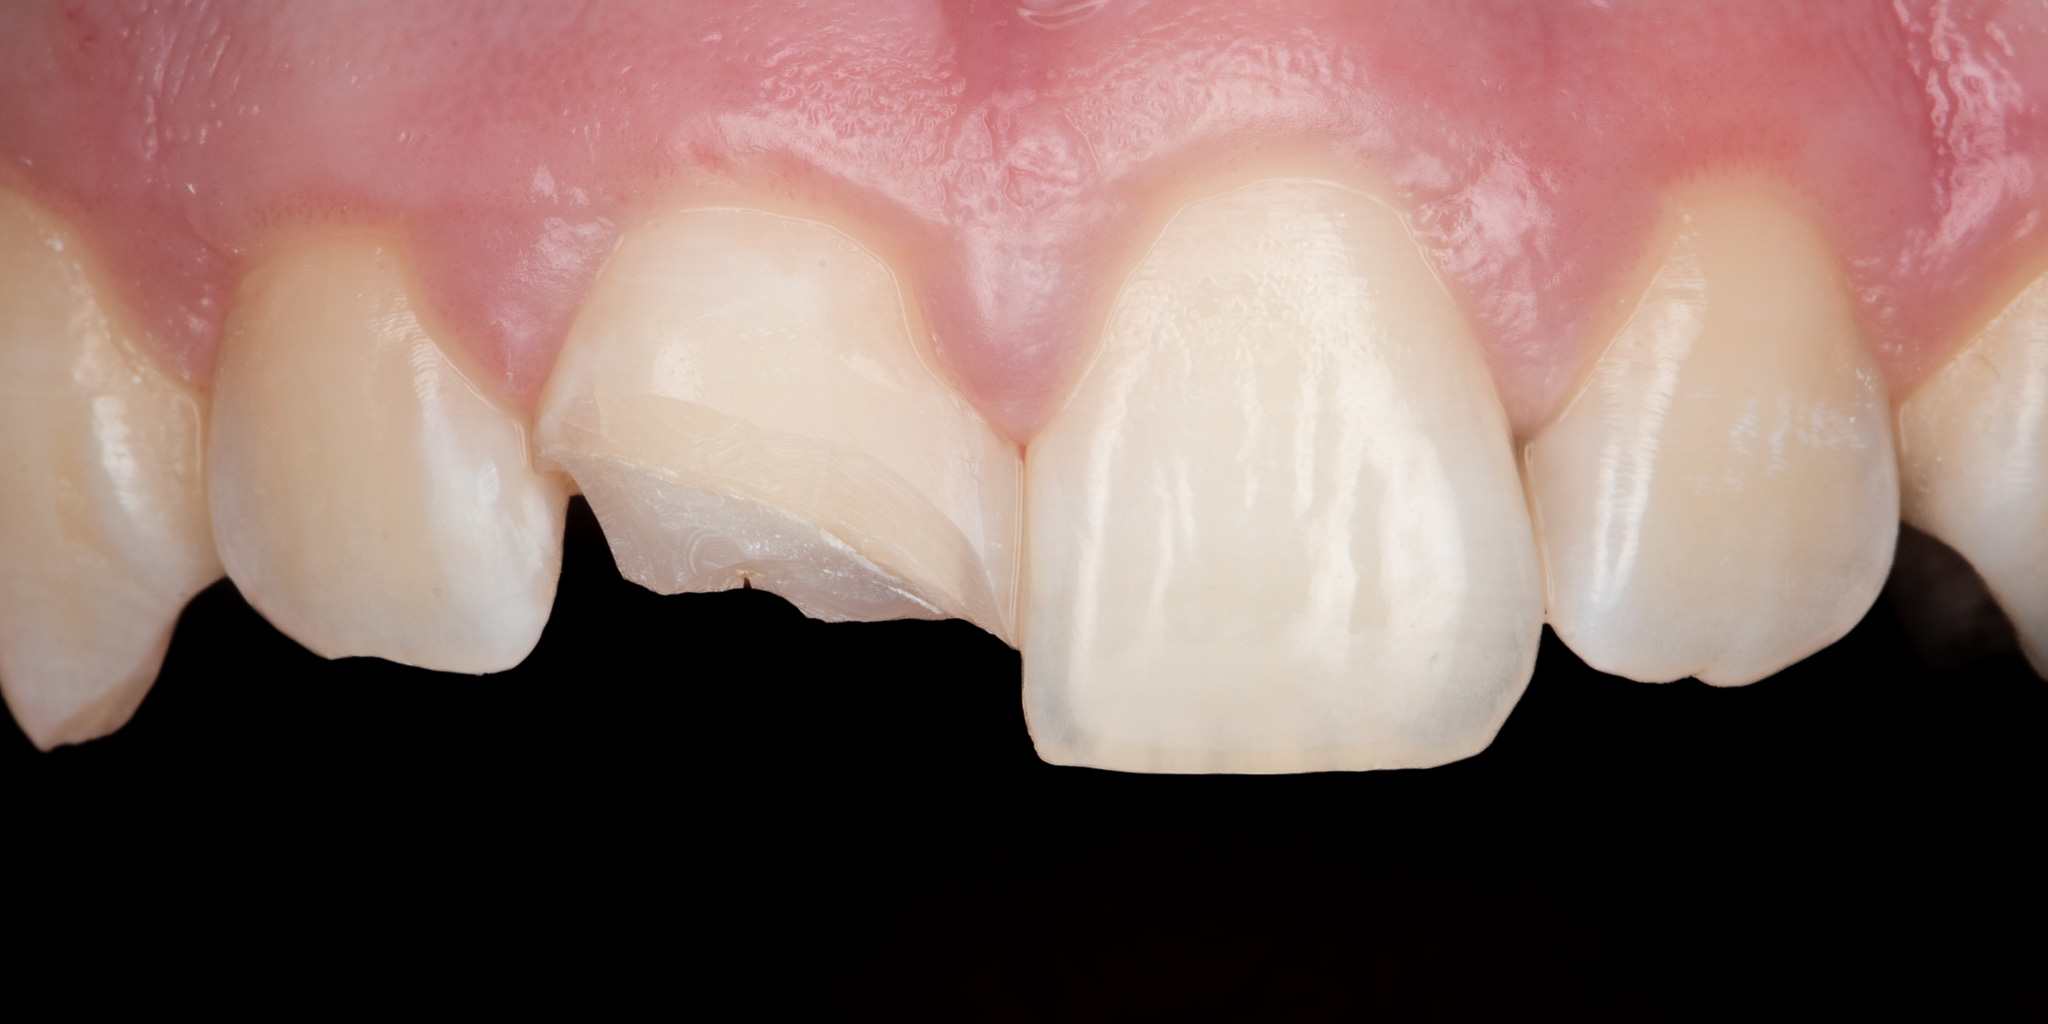

Pacjent 1

Pacjent zgłosił się podając złamie prawego siekacza centralnego (jedynki) w wyniku urazu. Wykonano estetyczną odbudowę biomimetyczną materiałem kompozytowym 3M™ Filtek™ Universal zapewniającym wysoką estetykę a także podniesioną odporność mechaniczną w porównaniu do konwencjonalnych wypełnień.